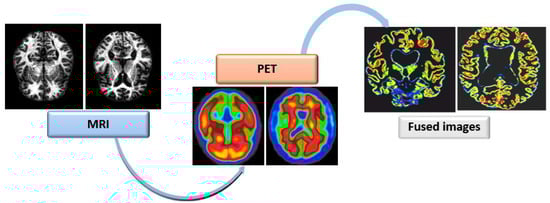

This study used a fusion of MRI and PET images to diagnose and categorize AD [11] extracted from the ADNI’s public dataset [23] (as shown in Figure 2). ADNI has primarily been designed to test if the serial MRI, PET, and basic subject information and ratings (neuropsychological assessments) can all be used to measure mild cognitive impairments (MCI), normal cohort (NC), and early Alzheimer’s disease (AD). Inspired by the outstanding achievement of medical image analysis [10,12,21], an FDG-PET image is fused with MRIs to achieve a multi-modal image fusion strategy. Due to the fact that the MRI and FDG-PET scans of each participant had several images captured at different times, the images of each subject were chosen based on the following steps:

Figure 2.

Image fusion architecture.

- Combine MRIs and PET images modality to a single picture area.